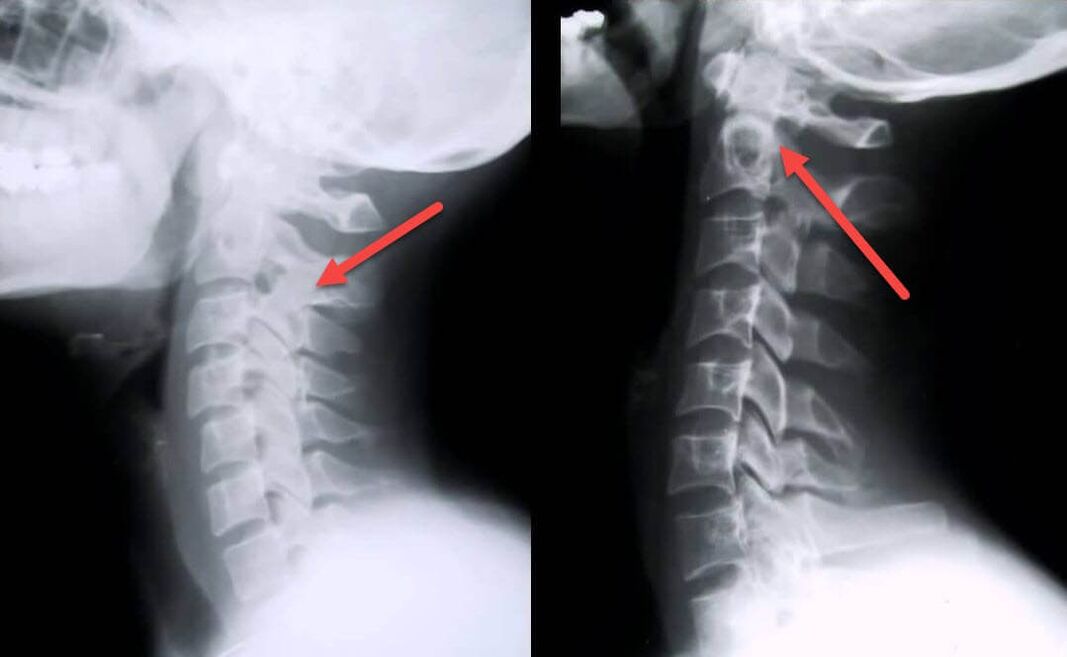

The most informative diagnostic procedure is radiography.Grade 1 pathologies correspond to the first or second radiological stage.The resulting images visualize the typical signs of the disease.

| X-ray stages of cervical osteochondrosis of the 1st degree | Characteristic signs |

|---|---|

| Phase 1 | Small changes in the curvature of the spine in the cervical region, affecting one or more segments |

| Phase 2 | Slight thickening of intervertebral discs, deformation of uncinate processes, direction of lordosis, small growths of bone structures. |